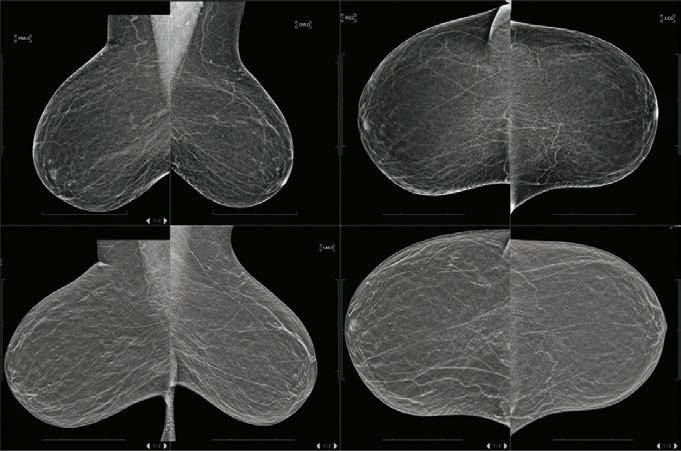

Figure 5. Mammography from 2019 (top) and 2020 (bottom).

margins were involved, and the mass comprises infiltrative sheets and clusters of malignant ductal epithelial cells with comedo-type necrosis. The tumor cells show markedly enlarged pleomorphic nuclei with vesicular chromatin and a distinct-toprominent nucleoli (Figure 2). Myoepithelial cell layer is absent. The tumor shows the following immunophenotypic profile: CK7 and GATA-3 diffuse positivity; GCDFP-15 and estrogen receptor (ER) patchy positivity; BNC5 immunostain confirms a clonal ductal proliferation with loss of the myoepithelial cell layer; CK20, p40, CK5/6, uroplakin-II, mammaglobin, CD56, synaptophysin, and S100 immunostains are all negative; and p16 immunostain shows equivocal patchy staining. Therefore, usual markers of breast origin (CK7, GATA-3, GCDFP-15, and ER) are positive, while usual markers of melanocytic, neuroendocrine, and urothelial primaries are negative (Figure 3). Hence, the diagnosis of a primary ectopic breast carcinoma of the vulva, histologic grade 3 (poorly differentiated). The pathologic staging for this case is a pT1b pNX (for lesions more than 2 cm or any size with stromal invasion more than 1.0 mm, confined to the vulva and/or perineum; and regional lymph nodes cannot be assessed). Prognostic markers revealed: ER is weakly positive (20%), progesterone receptor (PR) is negative (<1%), and HER2 oncoprotein is positive (3+). The tumor cells show the usual profile of an invasive ductal carcinoma of breast origin. Evaluation of receptor protein expression is performed by visual analysis of formalin-fixed paraffin-embedded immunostaining of the invasive tumor using FDA-cleared antibodies and protocols with estrogen receptor protein (Ventana SP1 antibody), progesterone receptor protein (1E2 antibody) and FDA approved HER2 oncoprotein (Ventana 4B5 antibody). ER protein expression is weakly positive with 20% nuclear positivity and 2+ average intensity score (range 0 to 3+). PR protein expression is negative with <1% nuclear positivity. Assay external control immunoreactivity is appropriate. No internal control was present in the analyzed tissue. False negative results may occur when no internal control ducts are present in tissue with negative reactivity in the tumor cells. Therefore, the results from specimens that are negative must be evaluated accordingly. HER2 oncoprotein expression is positive with 3+ average membranous intensity. Positron emission tomography/computed tomography (PET/CT) scan was performed which showed multiple enlarged and fluorodeoxyglucose (FDG) avid retroperitoneal, bilateral iliac chain and pelvic lymph nodes most consistent with metastatic disease. Several indeterminate subcentimeter, mildly FDG avid bilateral subpectoral lymph nodes were visualized as well. Hypermetabolic osseous lesion involving the left T12 lamina is consistent with metastatic disease (Figure 4). There is an indeterminate 8 mm left upper lobe nodule with no abnormal FDG activity seen on CT, likely too small to be seen on PET. Mammogram showed no evidence of malignancy (BIRADS Category 1), and past mammography from 2019, 2018, 2016 and 2014 were all negative (Figure 5). The patient has a history of hypertension, diabetes mellitus Type 2, dyslipidemia, iron deficiency anemia, osteoarthritis, rheumatoid arthritis, sleep apnea, chronic diarrhea, and nausea. Past surgical history includes Cesarean section, dilation and curettage, fluorescein angioscopy, bevacizumab injection, and retina treatment (photocoagulation). There is no significant family history of cancer. The patient is being managed by a hematology oncology provider. A biopsy of lymph nodes or bone was requested but was not feasible. Initial treatment options were followed: chemotherapy with paclitaxel, trastuzumab and pertuzumab. A cycle is every 21 days with close monitoring of heart function. Echocardiogram was obtained prior to initiating the treatment to assess the baseline cardiac function which was within normal limits. Denosumab is given to prevent skeletal events with the plan for restaging every three to four cycles. Following the initiation of the treatment, Taxol was changed to Abraxane due to allergic reaction, even with oral high dose dexamethasone. A cycle is 21 days: 2 weeks on and 1 week off. The patient reported severe depression and anxiety, and she was referred to palliative care and support group. The patient also reported a new onset headache, which prompted CT scan of brain which was within normal limits. The patient declined MRI due to claustrophobia.